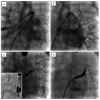

The goals of the procedure are set jointly by the cardiology and surgical teams. Quantifying risks can also be problematic but they are probably similar to the risk of performing a diagnostic catheter study in a pulmonary hypertensive child. These risks have been considered in the literature and can be used as a guide [5454. Taylor CJ, Derrick G, McEwan A, Haworth SG, Sury MR. Risk of cardiac catheterization under anaesthesia in children with pulmonary hypertension. Br J Anaesth. 2007;98:657-61. ]. General anaesthesia is indicated and appropriate planning with the anaesthetist and post-procedure intensive care team should be arranged. One unit of blood needs to be readily available. Femoral venous access improves the chances of crossing the atrial septum through a patent foramen ovale if present. Access from the inferior caval vein also improves the catheter approach to the right-sided veins which can be difficult, though not impossible, to access if approaching from the internal jugular vein. For interrupted inferior caval vein with azygous continuation or bilateral femoral vein occlusion a transhepatic approach is favoured over the internal jugular vein approach for the same reason. We routinely place a 4 French (Fr) arterial sheath for arterial pressure monitoring, confirming a normal left ventricular end-diastolic pressure and to check arterial blood gases periodically. As procedures can be prolonged and are performed on the left side of the circulation, full heparinisation is appropriate after crossing the atrial septum in case transseptal puncture is necessary (heparin sulphate 100 IU/kg iv and then to maintain an ACT >200s). Systemic emboli is a common complication either from the long sheaths and long duration of the procedure or from thrombus in partially obstructed or near atretic veins that are then openend during the procedure. Transseptal puncture in infants is potentially hazardous as the left atrium is usually small and the atrial septum hypertrophied. We prefer to use a radio-frequency wire with a coaxial catheter such as the system available from Baylis (Montreal, QC, Canada) as this affords greater control ( Figure 4 ) but standard Brockenbrough needle approaches can be used in older children. Prophylactic antibiotics are given by some to cover the procedure. A blood gas should be checked before recording haemodynamic data and the endotracheal tube position confirmed. The lung fields should be viewed on brief fluoroscopy for lobar collapse.

The stenosed pulmonary vein should be cannulated as distally as possible to improve wire position. Several wires can be used and the choice will depend to some extent on the age of the child and the catheter position achieved. The floppy part of the wire needs to be beyond the stenosis to provide a secure scaffold for delivering and retrieving various-sized angioplasty balloons. 0.014’ coronary wires such as heavy weight or middle weight wires are particularly useful in infants (Abbott Vascular, Abbott Park, IL, USA). Two coronary wires (‘buddy wire’) can increase the amount of support and aid tracking of the angioplasty balloon ( Figure 4 ). Several coronary wires may need to be tried if it is difficult crossing a tight lesion.

Results from stent placement in PVS are difficult to evaluate by comparison with angioplasty or cutting balloon angioplasty as they are likely to be used when the initial angioplasty result is regarded by the operator as sub-optimal ( Figure 6) [77. Mendelsohn AM, Bove EL, Lupinetti FM, Crowley DC, Lloyd TR, Fedderly RT, Beekman RH 3rd. Intraoperative and percutaneous stenting of congenital pulmonary artery and vein stenosis. Circulation. 1993;88:II210-7.